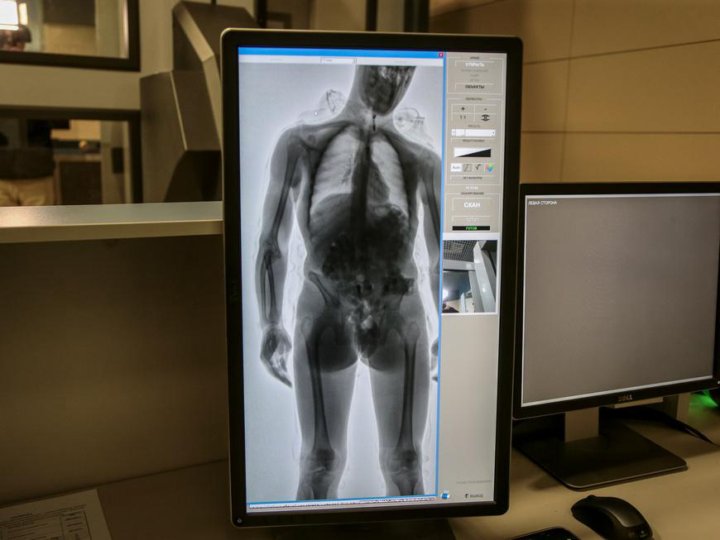

Здоровье на первом месте: диагностика и лечение через рентгеноскопию конечностей

Раздел: Снимки-откровения